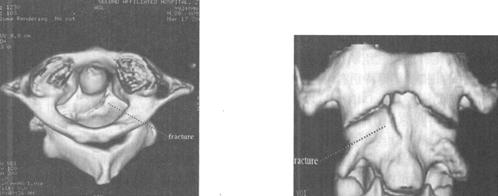

CT在脊柱脊髓损伤中应用很广泛,横断面成像是诊断脊椎骨结构创伤的主要手段,它可显示X线平片不易显示的细微骨折和小关节脱位,并能够很好地显示骨性椎管的情况,可为评价脊髓受压情况提供重要的影像学信息。螺旋CT扫描技术可对患者进行快速连续多部位成像,并支持多平面及三维成像。因而CT扫描对理解脊柱复杂解剖部位,发现细微病变有十分重要的临床意义(图7-4至图7-6)。甚至明显侧弯变形脊柱的冠状面重建亦可通过严格按照脊柱弯曲度改进的软件而获得。单纯轴位扫描很容易漏诊与CT断层面平行的骨折,例如,发生在齿突基部和胸腰水平的创伤,在横断位扫描中不能显示横断水平的骨折线,但在高质量的冠状、矢状和三维的重建图像中显示良好(图7-7至图7-10)。

图7-7、图7-8 多排螺旋CT2D重建,显示C2齿状突基底部骨折

图7-9、图7-10 多排螺旋CT3D重建,显示骨折线走行及累及骨表面